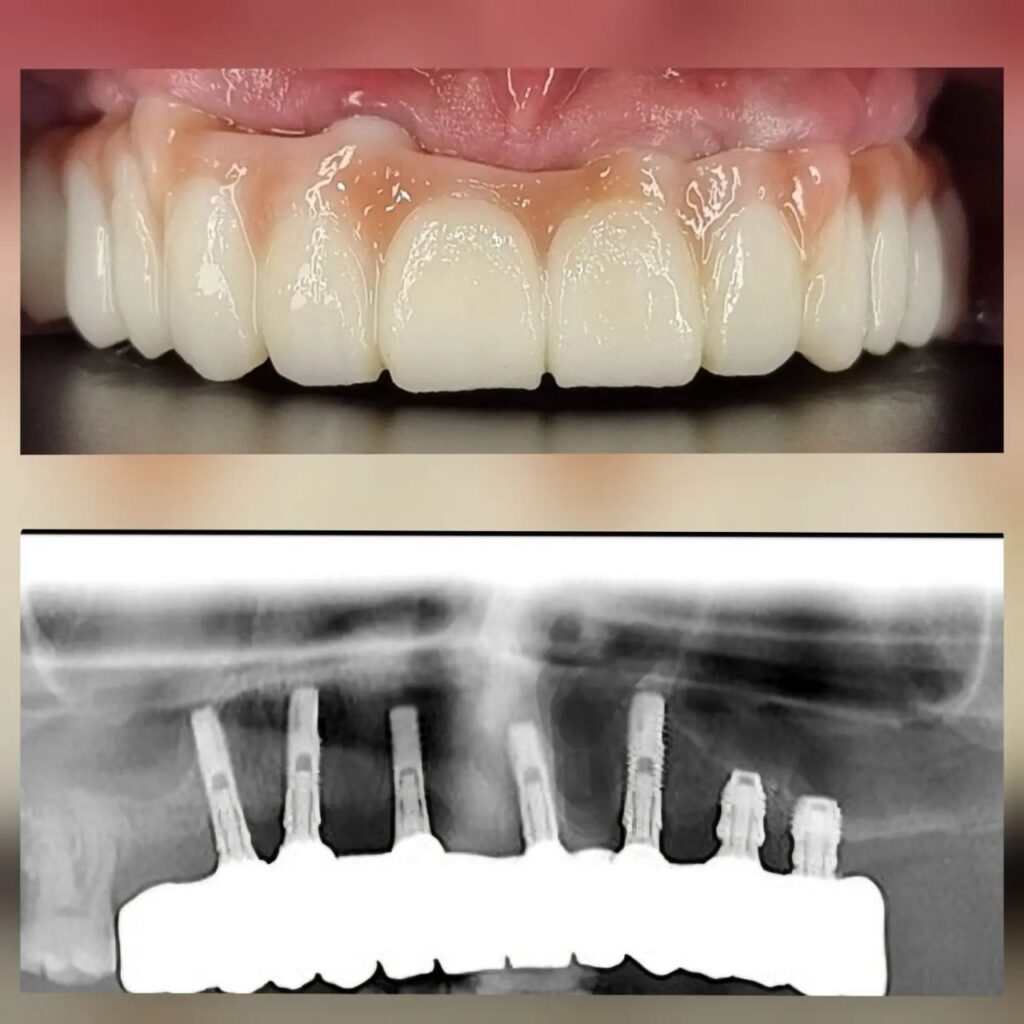

کاشت ایمپلنت دندان

اطمینان حاصل کردن از اینکه دندانهایتان به نحوی زیبا و طبیعی جایگزین شدهاند، از اهمیت بسیاری برخوردار است. ایمپلنت دندان به عنوان یک روش درمانی دائمی در دندانپزشکی شناخته میشود که حاصل آن، یک دندان زیبا و طبیعی در دهان شما خواهد بود.

هرچند که این روش درمانی هزینهی بیشتری نسبت به روشهای دیگر دارد، اما ارزش زیبایی که ایجاد میکند، قابل انکار نیست. ایمپلنتها به قدری شبیه به دندانهای طبیعی هستند که به سختی میتوان آنها را از دیگر دندانها تشخیص داد.